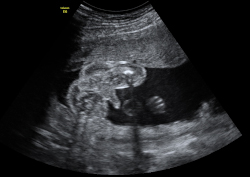

En la ecografía en 3D vemos a un bebé de 20 semanas de gestación se tapa la cara con ambos brazos y aprieta los puños. Se trata de un gesto innato que mantendrá en la cuna durante los primeros meses de vida.

Imagen de bebé tapándose la cara con ambos brazos

Ecografía Embarazo 2D y 3D - SEMANA 20